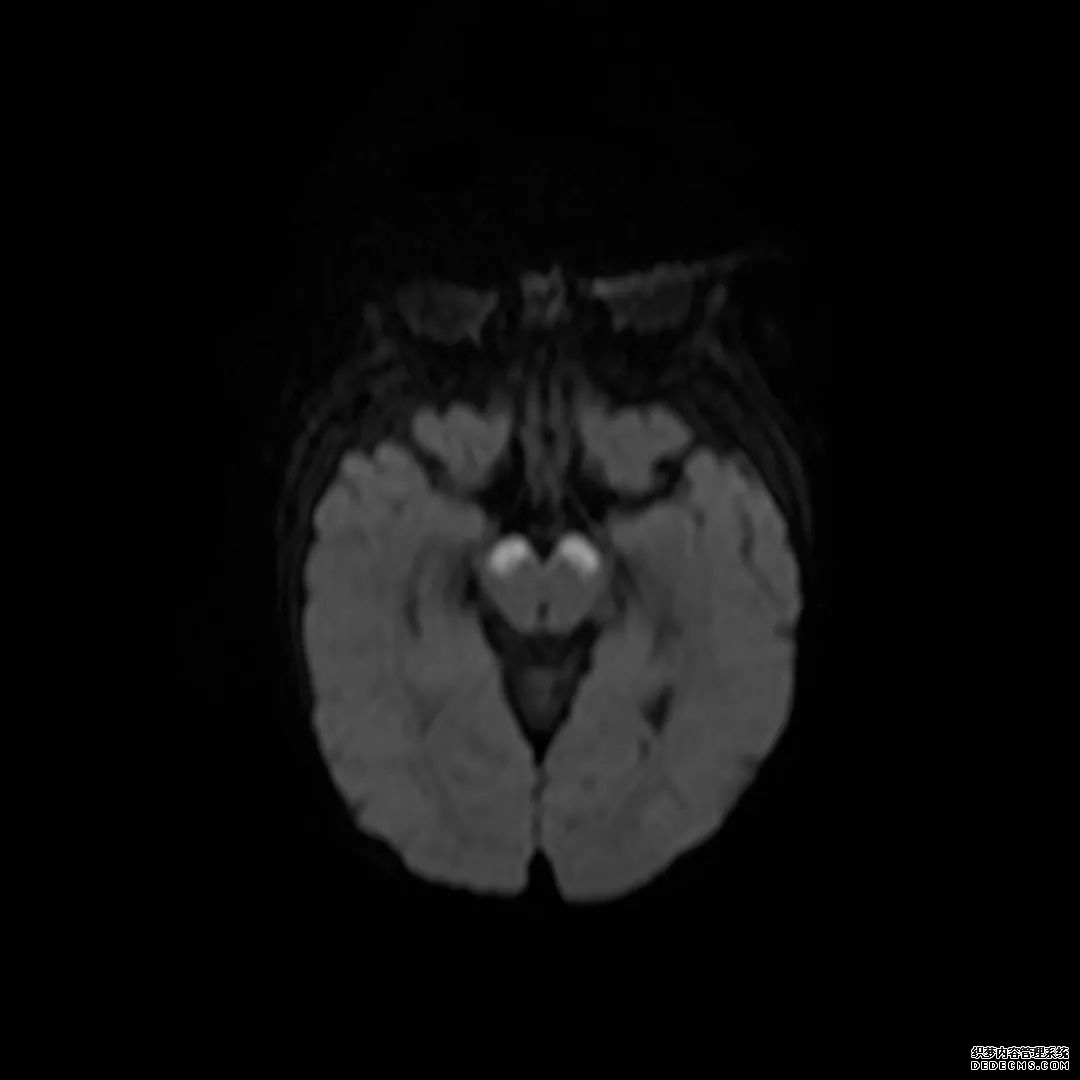

脑MRI显示尾状核、扁豆状核和脑梗头部T2/FLAIR呈双侧对称异常高信号。扩散限制涉及这些区域,其特征是扩散加权DWI(B-1000)上的高强度,ADC图上相应的减弱强度。

低血糖性脑病是一种代谢性脑病,它是由脑细胞对葡萄糖的供应和使用之间的不平衡引起的。脑MRI,尤其是DWI是诊断和预测该病预后的重要工具。

这个病例说明了低血糖脑病,有典型的病史和血液指标,结合MRI表现,DWI为诊断提供了最好的线索。